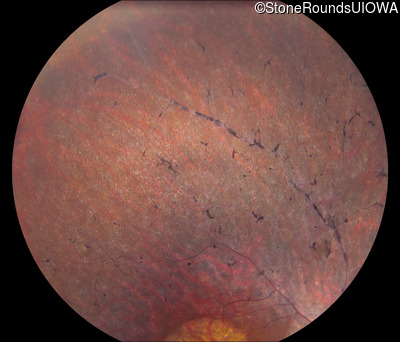

Visit at age: 63 years

Fundus Photography - Right - 20/25

Exemplar